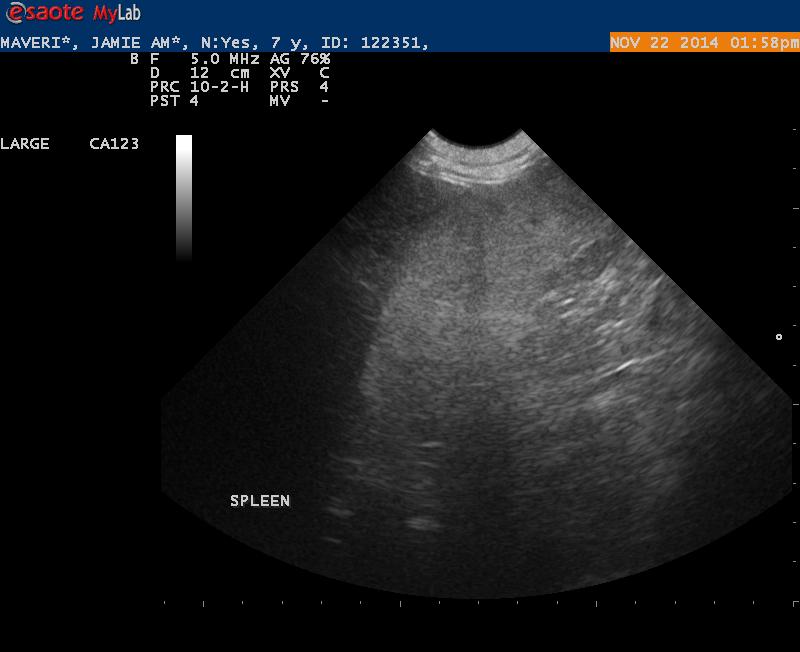

Maverick is a 7 1/2 year old Lab with 2 fairly large cutaneous mast cell tumors.

On x-rays the spleen was prominent but not overly enlarged.

Ultrasound findings were within normal limits. I did not appreciate any lymphadenopathy.

The spleen on first glance appeared to be normal- but when I went back and looked at my images I was wondering if the echotexture was a bit coarse.

1. Do you see any abnormalities with this spleen making it worthwhile to get an aspirate?